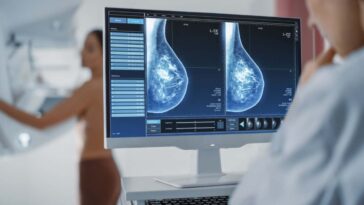

Comment les IRM peuvent détecter l'apparition de la maladie de Parkinson avant l'apparition des symptômes